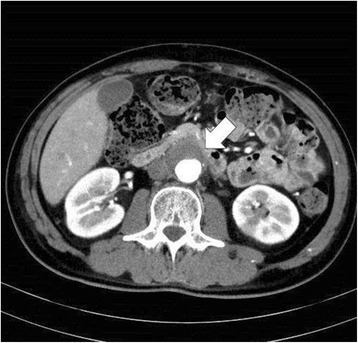

High morbidity enlargement and dilation of a region of the abdominal aorta (150% of normal diameter), with risk of rupture proportional to size

Saccular (localized) vs Fusiform (circumferential)